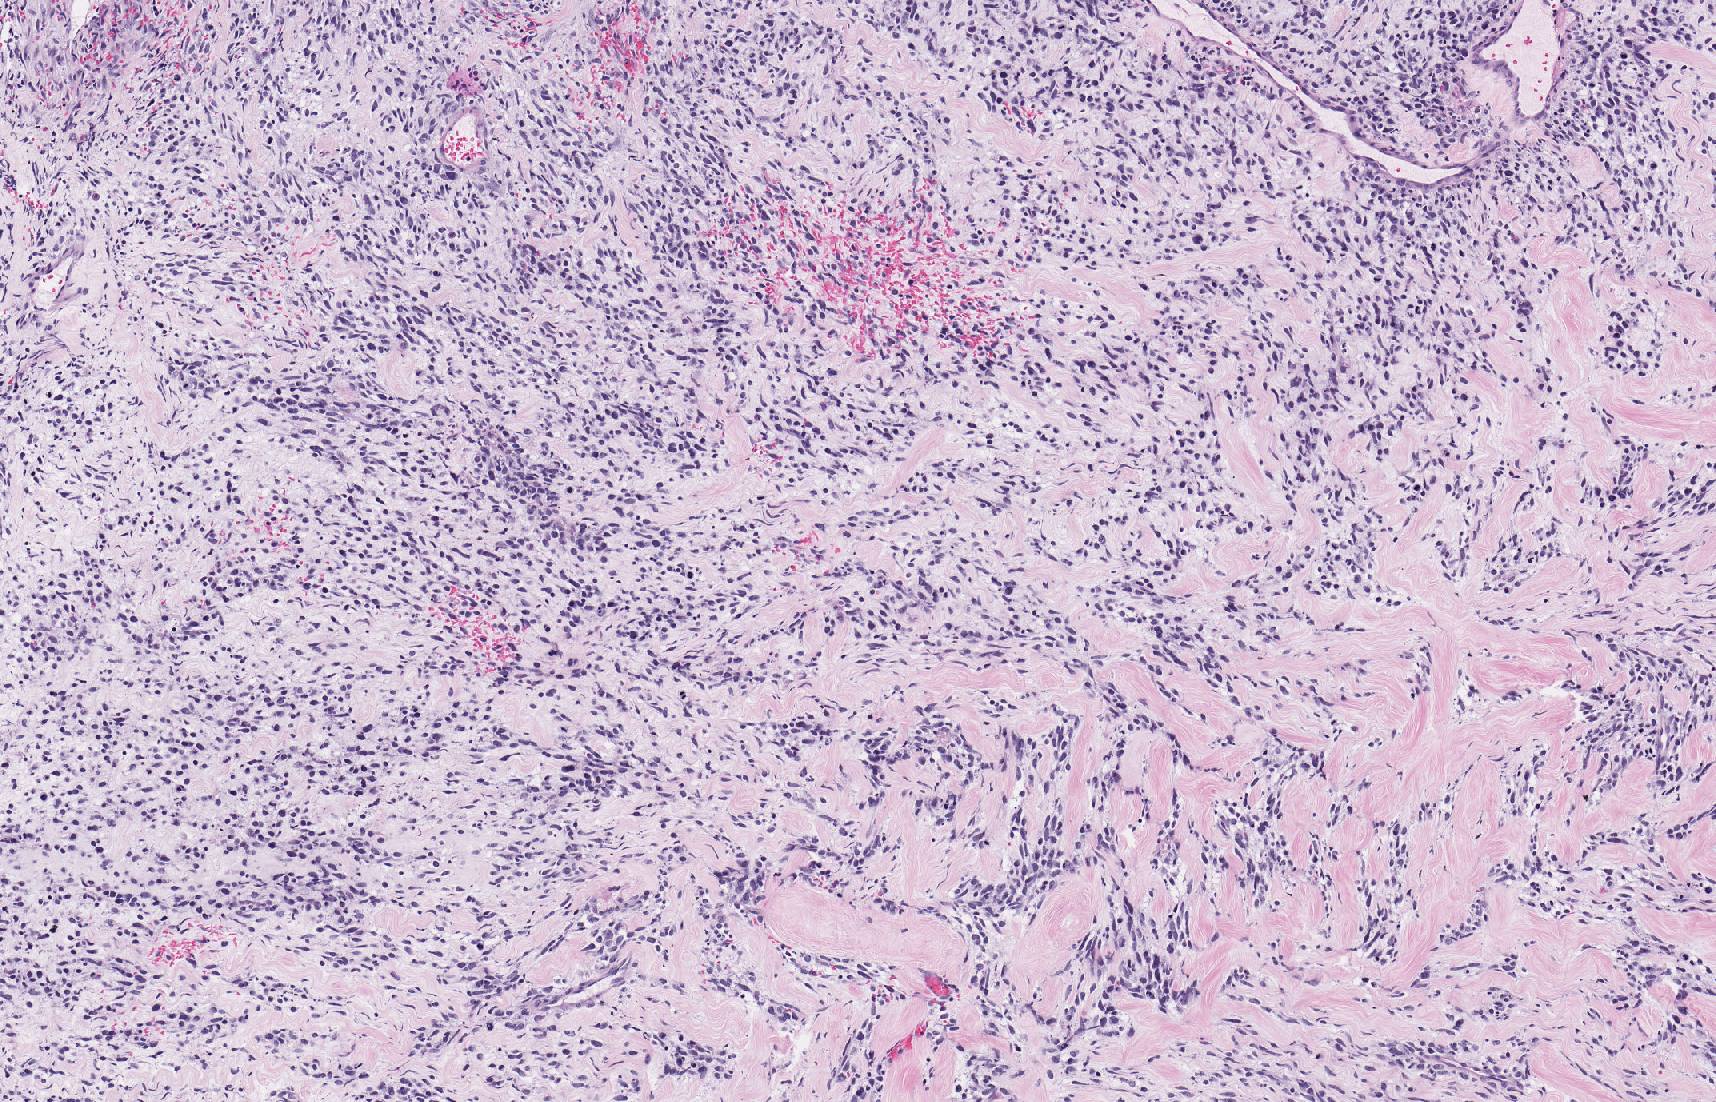

Proliferation of epithelioid and spindle cells, permeating malformed

Proliferation of epithelioid and spindle cells, permeating malformed Spindle Epithelioid Cells the variable, atypical, spindle to epithelioid tumor cells are admixed with prominent inflammatory cell infiltrate. A diverse array of tumors arises within the narrow confines of the sinonasal tract. soft tissue myoepithelioma lacks the sharply demarcated lobules of dermal nerve sheath myxoma, and is. spindle cell lesions can occur in head and neck skin, in the soft. Spindle Epithelioid Cells.